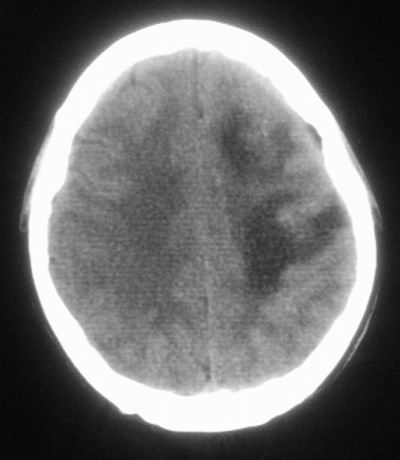

治疗三天后复查ct片示:

治疗三天后复查ct:除左侧额顶叶血肿外。左侧额叶另见片状低密度灶,密度不均匀,境界不清;考虑脑梗塞。

建议:必要时行进一步检查排除烟雾病。